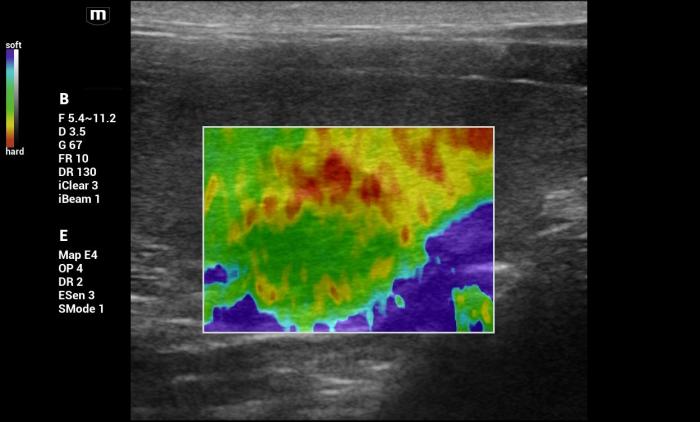

Además de la medición cuantitativa de la velocidad de la onda de corte expresada en metros por segundo (m/s), el sistema Natural Touch Elastography® (Mindray MX7) dispone de una función complementaria de representación cualitativa y semicuantitativa de la rigidez tisular (Figura1-4). Esta herramienta permite asignar valores numéricos y porcentajes relativos al grado de dureza o blandura del tejido evaluado y facilita la comparación visual y numérica entre diferentes regiones de interés dentro de un mismo órgano, incluyendo la relación entre una lesión focal y el parénquima esplénico adyacente.

De acuerdo con la documentación técnica del fabricante, esta funcionalidad se basa en el análisis de la respuesta tisular al impulso acústico y en algoritmos de seguimiento por radiofrecuencia, lo que contribuye a una evaluación intraorgánica más precisa. Si bien estos valores no sustituyen las mediciones cuantitativas en m/s ni cuentan con puntos de corte validados para la diferenciación diagnóstica, su utilización aporta información complementaria útil para la interpretación clínica de los hallazgos elastográficos, especialmente cuando se integra con la evaluación en modo B y Doppler.

Hallazgos elastográficos (Natural Touch Elastography®): la lesión mostró una rigidez similar al parénquima esplénico circundante, con valores que no superaban los rangos normales descritos para bazo canino3,4 (Figura 9-10). La uniformidad de las mediciones, sin artefactos relevantes y con estabilidad entre adquisiciones consecutivas, aumentó la confiabilidad de la evaluación.

Hallazgos elastográficos (Natural Touch Elastography®): El análisis mediante NTE evidenció una rigidez baja, comparable al parénquima esplénico normal, sin zonas internas de aumento marcado de velocidad (Figura 15-16). Las mediciones fueron consistentes, con buena calidad técnica y sin artefactos significativos.